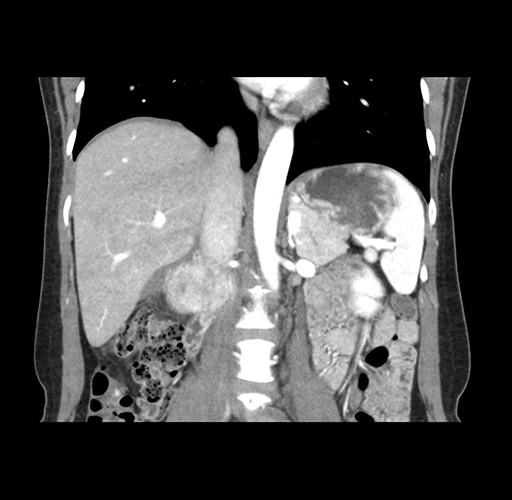

Imaging Analysis

Look through the patient's CT scan to identify any areas of concern for the necessary procedure.

Based on your CT findings, which issue(s) would give reason for "planned slowing down moment(s)" in this case?